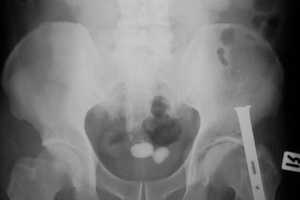

Отсутствие тени на обзорной рентгенограмме не исключает наличие камня мочевого пузыря. Примерно в 50 % случаев камни не определяются на обзорных рентгенограммах. Рентгенонегативный камень можно выявить при цистографии. Лучшим и наиболее точным методом диагностики камней мочевого пузыря является цистоскопия. Ни один камень не будет пропущен при непосредственном осмотре мочевого пузыря.